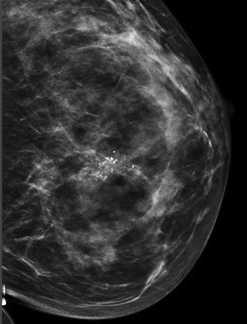

calcificationsBreast calcifications are calcium deposits that develop within breast tissue. They are too small to be felt, but they are commonly found on mammograms, appearing as bright white spots. Calcifications are usually benign and are especially prevalent in postmenopausal women.[1] They can appear as the result of age, a past infection, injury, surgery, or breast implants.[2]

Two types of calcifications may be found on a mammogram, macrocalcifications and microcalcifications.  Macrocalcifications appear large and round on a mammogram any are typically spread throughout the breast tissue in a seemingly random pattern.  Microcalcifications, on the other hand, are smaller and irregularly shaped.[3] Although both forms are usually benign, certain patterns of microcalcifications warrant further follow-up.  Detection of these patterns may be the earliest sign of developing breast cancer.[4]

When calcifications are detected on a mammogram, the radiologist examines magnified views to get more information about their size, shape, and pattern of distribution.  Based on this information, the calcifications are classified as benign, probably benign, indeterminate, or suspicious.